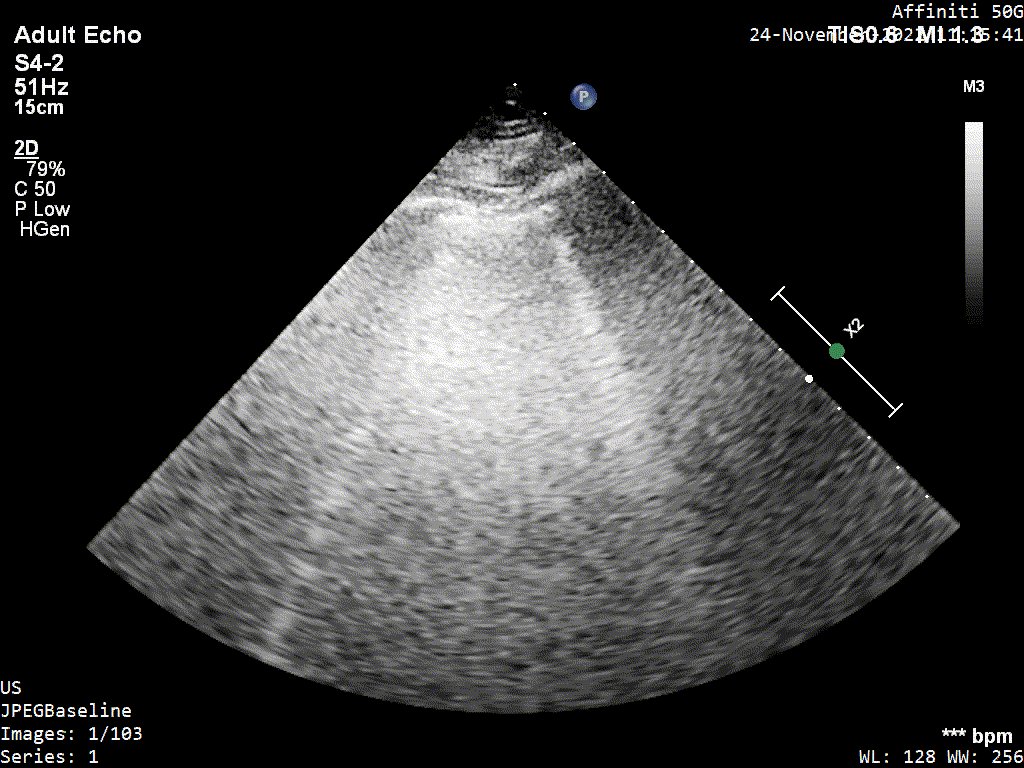

5/ PLAX

22/ I went back to see her a week later because I was really curious to see her in a 'lower flow state'. I wanted to check the aortic valve (is there stenosis?) and also the mitral (some hidden nuggets there).

Intraventricular obstruction almost disappeared...

23/ Mean aortic gradient was only 17hgmm (reduction from 34). This corresponds to NO aortic stenosis (cutoff 20hgmm, Vmax 2.5m/s) and I reported it as aortic sclerosis.